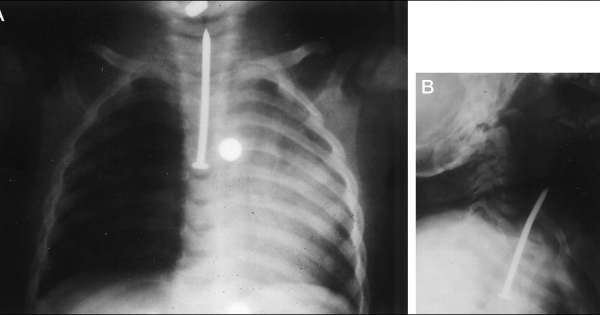

العملات المعدنية هي واحدة من العناصر الأكثر شيوعًا التي يبتلعها الأطفال ، إذا ابتلع طفلك عملة معدنية، اصطحبه إلى طبيب الأطفال أو إلى قسم الطوارئ في المستشفى قد تكون الأشعة السينية ضرورية للتأكد من أن العملة تمر عبر الجهاز الهضمي بشكل طبيعي.

- ممر الجهاز الهضمي هو ممر الأمان لأنه يعني تجاوز العملة المعدنية الجهاز التنفسي ووصولها للجهاز الهضمي وهنا يسهل التخلص منها عن طريق البراز بدون أي إجراءات أيا كان مكانها سواء في المعدة أو الأمعاء، وفي هذه الحالة لا يظهر على الطفل أي أعراض، حتى أن تنفسه يكون منتظم.

- و بخضوع الطفل لعمل أشعة “اكس” على البطن على أن يكون الطفل واقفا لتحديد مكانها فقط، خاصة أنها لن تتسبب في وجود أي مشكلة في الجهاز الهضمي، وأكد أنه لا يكاد يمر أسبوع إلا وقد تخلص الجسم منها.

- إذا علقت العُملة داخل موضع ما بالجسم ستظهر علامات على ذلك من العلامات القئ، وألم الصدر والبطن إذا كانت عالقة في المرئ أو المعدة. أما إذا علقت على جدار الأمعاء فقد تؤذي الجدار، ومن علامات وجودها في ذلك الجزء وجود صوت غريب عند إخراج البراز أو وجود نزيف معه. من الهام أن يلجأ الآباء إلى الطوارئ، وألا تتم محاولة إخراج العُملة بالإصبع لأن ذلك سيضر الطفل أكثر.

- عند حدوث هذه الحادثة، أو الشك في حدوثها، لا ينبغي الانتظار وإنما طلب الطوارئ على الفور، وإجراء الفحص بالأشعة السينية (إكس)، واتباع التعليمات الطبية.